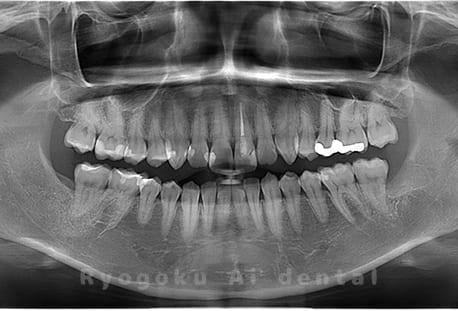

Case01

- 原因

- 水平埋伏智歯

- 治療内容

- 下顎の水平埋伏智歯を抜歯

<リスク・副作用>

手術後は痛み、腫れ、痺れなどの副作用が生じる場合があります。